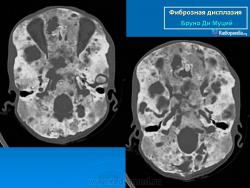

Фиброзная дисплазия

Для фиброзной остеодисплазии, или болезни Брайцева-Лихтенштейна, характерно нарушение костеобразующей функции мезенхимы, проявляющееся в одной или нескольких костях, что ведет к их деформации и образованию в них очагов разрежения, обычно отграниченных от здоровой ткани кости склеротической каймой. Объем пораженной кости при этом может быть увеличен. Чаще поражаются трубчатые кости, но характерные изменения могут отмечаться и в костях черепа. В таких случаях возможны облитерация придаточных полостей носа, деформация глазниц, сужение отверстий в основании мозгового черепа и в лицевом черепе, ведущее к нарушению функции проходящих через них нервов и сосудов. Заболевание, возможно, наследственное, проявляется с детских лет. Описал в I927 г. отечественный хирург В.Р. Брайцев (1878-1964), несколько позже - американский патологоанатом L. Lichtenstein (1906-1977).

Полиостотическая фиброзная дисплазия у пациента с синдромом Маккьюн - Олбрайта.